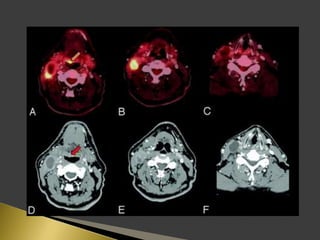

 PET using the radio-labeled glucose analog 18F-FDG has great

importance in lymph node imaging.

 PET supplies a semi-quantitative metabolic characterization of

tissues that may help to predict tumor behavior.

 The sensitivity and specificity of 18F-FDG PET for identification

of lymph node metastases on a neck level-by-level basis were

higher than those of CT/MRI.

 The incorporation of functional information derived from PET

has the potential factor to improve prognostic stratification and

treatment planning for patients.

 Patients were instructed to fast for 6 h before the PET study.

 18F-FDG was administered intravenously.

 For PET/CT scans, oral contrast was administered to patients

during the uptake time.

 No IV contrast material was administered for CT scans.

 Head to mid thigh scans were obtained for all patients.

 PET and CT images were acquired 50 min after the injection of

18F-FDG.

 PET, CT, and fused PET/CT images were available for review

and were displayed in axial, coronal, and sagittal planes.

 PET data were displayed as non-corrected and attenuation-

corrected images as well as in a rotating MIP.

 Area of increased 18F-FDG uptake with intensity higher than

that of surrounding tissues and did not correspond to the

physiologic bio-distribution of the radiotracer, were defined as

positive.

 18F-FDG activity only in areas of the physiologic tracer bio-

distribution or no sites of increased uptake were considered

negative.

 The highest activity within a region of interest was measured.

 The standardized uptake value (SUV) was determined as the

highest activity concentration per injected dose per body weight

(kg).

 18F-FDG uptake was graded visually on the following 5-point

scale:

 0-definitely benign, no uptake.

 1-probably benign, 2.3 (range, 1.4–4.0).

 2-equivocal, 2.6 (range, 1.4–4.4).

 3-probablymalignant, 3.5 (range, 2.1–7.9).

 4-definitely malignant, 6.6 (range, 2.6–24.5).

 SUV of 3.1 was used as the cutoff for positive PET results.